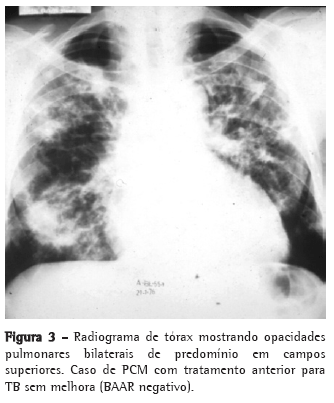

As queixas clínicas, os dados de exame físico e as alterações radiológicas apresentadas por esses doentes, na maioria das vezes, não permitiram a diferenciação segura entre as duas doenças (Figuras 2, 3 e 4).

Por sua vez, a TB acomete ambos os sexos em qualquer idade, com a maioria dos pacientes se apresentando sintomáticos, com exame físico comprometido e alterações radiológicas, em geral, de predomínio em segmentos superiores e posteriores, podendo também ser bilaterais.